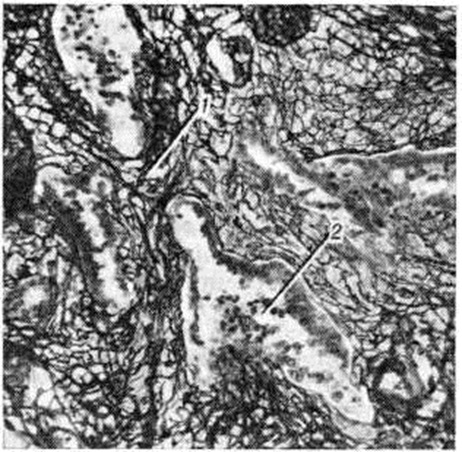

Рис. 1.

Микропрепарат лёгкого при сетчатом лимфогенном пневмосклерозе, склероз фиброзной прослойки: 1 — лимфатические фолликулы, 2 — утолщённые коллагеновые волокна; окраска гематоксилин-эозином; ×150.

В фиброзных прослойках микроскопически отмечается утолщение коллагеновых волокон, увеличенное количество лимфатических, фолликулов (рисунок 1), расширение лимфатических, сосудов, заполненных сгущённой лимфой. При обострении воспаления в фиброзных прослойках, прилегающих к пневмоническим очагам, коллагеновые волокна раздвигаются пикринофильной жидкостью. Впоследствии в этих участках развивается гиалиноз. Из-за того что сетчатый лимфогенный Пневмосклероз протекает без клеточной инфильтрации, его раньше ошибочно называли бесклеточным. На рентгенограммах сетчатый лимфогенный Пневмосклероз имеет вид усиленного лёгочного рисунка, что иногда ошибочно трактуется как интерстициальная пневмония, однако фиброз не выходит за пределы прослоек и не распространяется на альвеолы, что наблюдается при пневмонии.